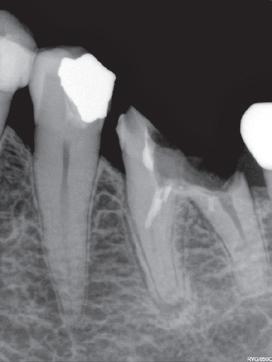

TrollBag for røntgensensorer

Supermyke trekk for sensorer og fosforplater. Helt uten lateks, lukt, smak og skarpe kanter. Lett å ta på og av, uten å ødelegge sensoren.

Tips: XL-trekket dekker både sensor og røntgenholder. En superenkel løsning som gjør hygienearbeidet mye enklere.

TrollBag for fosforplater

Supermyke poser for fosforplater.

Helt uten lateks, lukt, smak og skarpe kanter. Lett å ta på og av.

Leveres på rull i praktisk dispensereske.

Dekker sensor.

3,6*22cm.

500-pk. Før 1.048,#1

734,-

Vnr. 6509

#13190089

Dekker sensor. 4,0*22cm. 500-pk. Før 1.048,#13190090

Vnr. 6500

Fosforplate #1 49x29mm. 500-pk. Før 1.298,-

Fosforplate #2 50x36mm. 500-pk. Før 1.298,-

Vnr. 7783 974,-

Vnr. 7784

#13190401 #13190402

-30% på alle TrollByte Kimera røntgenholdere

Gjelder til 15.11.2024

TrollByte Kimera finnes for alle typer sensorer, fosforplater og film. TrollByte enkel å bruke. Stive, robuste holdere som gir deg full kontroll når du skal ta bilde. Ingen artefakter på bildene fra holderen. Kan autoklaveres. Produsert av miljøvennligere bioplast - enda et viktig miljøtiltak.

Vi hjelper deg å finne riktig. Ring oss på telefon 66892050, på post@td.no eller på LiveChat på www.td.no

Kompakt og stiv holder for enkelt å ta bitewing. 3-pk røde holdere (var tidligere rød/sort). Før 1.499,-

Startsett m/én av hver TrollByte Kimera rød, gul og blå, samt siktering og bittblokk. 3-pk. Ønsker du bare én farge så velg et av settene nedenfor. Før 1.499,-

Stående holder for periapikale opptak. Siktering og bittblokk følger med. 3-pk blå. Før 1.499,-

1.049,3-pk

Periapikal liggende (gul)

Liggende holder for periapikale opptak og bitewing. Siktering og bittblokk følger med. 3-pk gul. Før 1.499,-

For indikatorbilder og sluttbilder. Sett med blå spesial endoholder for stående, og gul spesial endoholder for liggende opptak. Med rød og grønn endobittblokk og siktering. Finnes for alle sensorer, plater og film. Før 1.799,-

Hva betyr TrollByte-nummeret?

Eksempel: 4305/2905. 43=lengden på sensoren, 29=høyden, 05=tykkelse på sensor, målt i millimeter. 4305=mål for gul holder / 2905=mål for rød/blå holder. Mål gjerne din sensor. Vi hjelper deg gjerne!